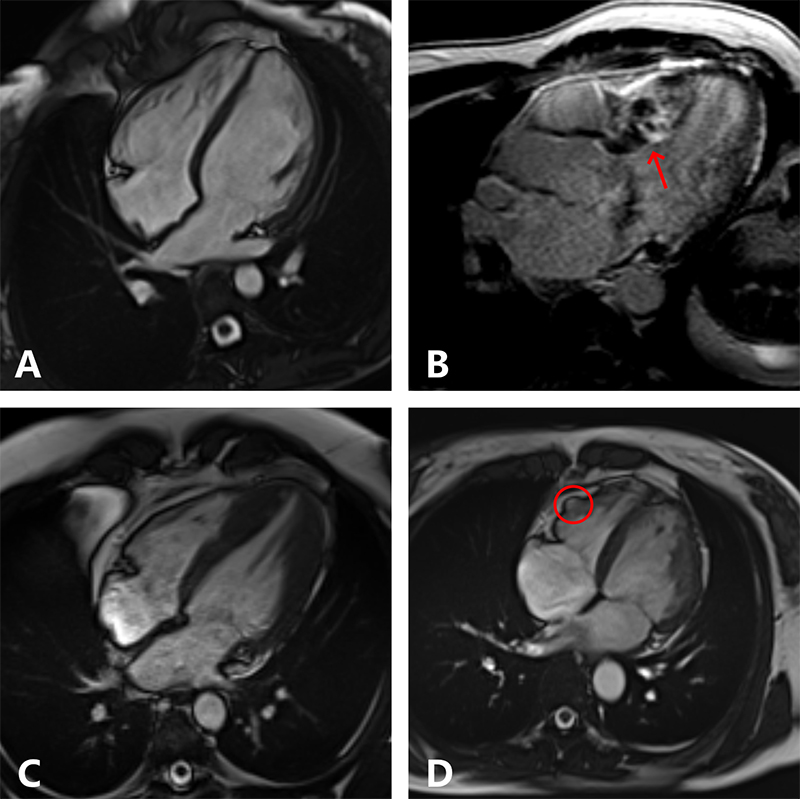

Cardiomyopathies are a heterogeneous group of conditions that affect the heart muscle, leading to structural and functional abnormalities.35 Cardiomyopathies are common aetiologies of SCD in young athletes.10 The most common types include hypertrophic cardiomyopathy (HCM), dilated cardiomyopathy (DCM), and arrhythmogenic cardiomyopathy (ACM).36 Each type presents distinct pathophysiological features that may overlap with physiological cardiac adaptation to exercise (figure 2).37,38 Various diagnostic tools and criteria have been developed to aid clinicians in this process, including ECG, transthoracic echocardiography (TTE), CMR, and genetic testing.39 In the absence of symptoms, the diagnosis may be triggered by the detection of ECG abnormalities, for example, in the context of pre-participation screening (figure 3). TTE should be the primary imaging modality for athletes with suspected cardiac pathology. CMR imaging may provide further insights into differential diagnosis. Beyond the very high spatial and temporal resolution, CMR allows tissue characterisation and may reveal myocardial oedema, tissue infiltration and myocardial fibrosis (figure 4).

Athletes in the ‘grey zone’ should be investigated with more detailed tests. CMR is crucial in this setting, providing an accurate assessment of LVWT, chamber volumes, and LV mass. Due to its excellent spatial resolution, this test enables the evaluation of apical hypertrophy and of subtle LVH that may not be adequately visualised by echocardiography. Notably, CMR detects hypertrophy in approximately 12% of HCM patients who were not diagnosed through TTE due to segmental LVH.54 In addition, CMR allows a detailed assessment of possible architectural changes of the LV, including hypertrophic, accessory and anteriorly displaced papillary muscles and apical systolic obliteration.53,55 The presence of myocardial crypts, which are defined as narrow, deep, blood-filled invaginations within the compacted myocardial wall, may suggest an underlying genotype positive status, even in the absence of other phenotypic signs of HCM.56 Furthermore, CMR offers the possibility of tissue characterisation through late gadolinium enhancement (LGE) imaging. Patchy LGE suggests interstitial myocardial fibrosis, which is often present in HCM patients, especially within the hypertrophied segments.57 Other techniques, such as T1 mapping, allow quantification of the myocardial extracellular volume (ECV), which correlates with diffuse interstitial fibrosis.58 A study on 50 HCM patients and 40 highly trained healthy athletes demonstrated that as LVH increases, extracellular compartment decreases in athletes but increases in HCM patients.59 The negative correlation between ECV and wall thickness in athletes suggests that the increase in LV mass in healthy myocardium is driven by cellular hypertrophy, whereas in HCM, it is due to extracellular matrix expansion and myocardial disarray.60

In athletes where the ECG and echocardiogram raise the suspicion of DCM, CMR may provide valuable insights, including an accurate assessment of LV volumes and the possible presence of mid-wall fibrosis, a feature that, if present, corroborates the diagnosis of DCM in the appropriate context.70 Moreover, ambulatory ECG monitoring, exercise stress echocardiogram and CPET may be helpful in the differential diagnosis. For instance, failure to augment cardiac output during exercise in athletes falling in the ‘grey zone’ (mild impairment of LV systolic function and significant LV dilatation at baseline echocardiography) is a red flag for DCM.71,72 Other features may suggest a pathological rather than physiological entity in this context, including high premature ventricular contractions (PVCs) burden (>2,000 per 24 hours) at ambulatory ECG monitoring, and propensity to develop frequent PVCs or non-sustained ventricular tachycardia (NSVT) during exercise tolerance test (ETT).73–76

When ACM is suspected, further investigations are warranted. CMR is the gold standard for the assessment of the RV and specifically to differentiate between normal and pathological findings.90 RV enlargement in athletes is usually accompanied by concomitant LV remodelling, reflecting a symmetrical adaptation of the heart to the haemodynamic changes induced by training.31 Regional wall motion abnormalities, such as dyskinesia, akinesia and aneurysms, as well as an RV/LV end-diastolic volumes ratio >1.2 and an impaired RV systolic function (RVEF ≤45%), are features that support ACM.33,34 Moreover, subepicardial and/or mid-wall LGE may corroborate the diagnosis.70 Other tests, such as ambulatory ECG monitoring and ETT can be helpful in the differential diagnosis. The presence of ventricular arrhythmias, such as a high burden of PVCs (>500 per 24 hours) and NSVT at ambulatory ECG monitoring are features that may point toward a diagnosis of ACM in the appropriate clinical context.33 In those with suspected ACM, ETT may reveal susceptibility to ventricular arrhythmias (either increased PVCs burden or NSVT) during exercise.33,91